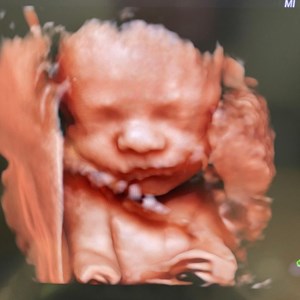

hjertelyd_scanningsklinik En tidlig scanning kan byde på overraskelser. Her er det 2 små ...

Dagens søde lille julenisse ❣️ Pige uge 30. Ca 1300 gram lækkerhed 😍

Sødeste lille pus ❣️#uge33 #3dlive #vægtscanning #babypics #hjertelyd #hjertelyd_scanning...